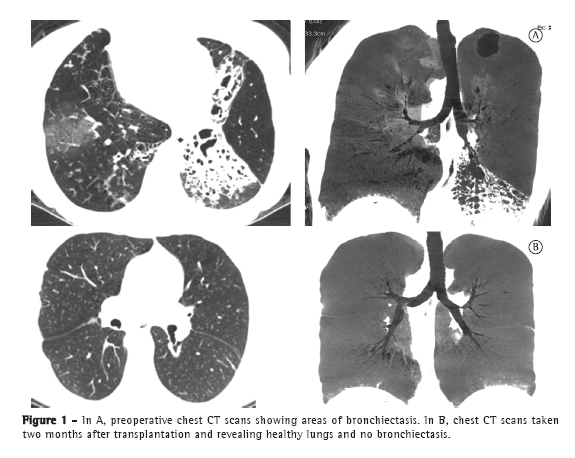

Thirteen years ago, we treated a 26-year-old female patient who had Kartagener syndrome and a history of recurrent pneumonia, together with localized bronchiectasis refractory to clinical treatment. Left middle lobectomy and right lingulectomy were indicated. The patient remained asymptomatic for 10 years, at which point the pneumonia recurred because of new foci of bronchiectasis (Figure 1), the patient showing significant lung function impairment requiring continuous oxygen therapy at 7 L/min.

At postoperative month 2, the patient had an FEV1 of 2.05 L (74.3% of predicted) and an FVC of 2.45 L (75.4% of predicted). At postoperative month 6, her FEV1 was 2.27 L (81% of predicted). At this writing (postoperative month 12), the patient had an FEV1 of 2.47 L (85% of predicted) and an FVC of 2.37 L (82.4% of predicted).